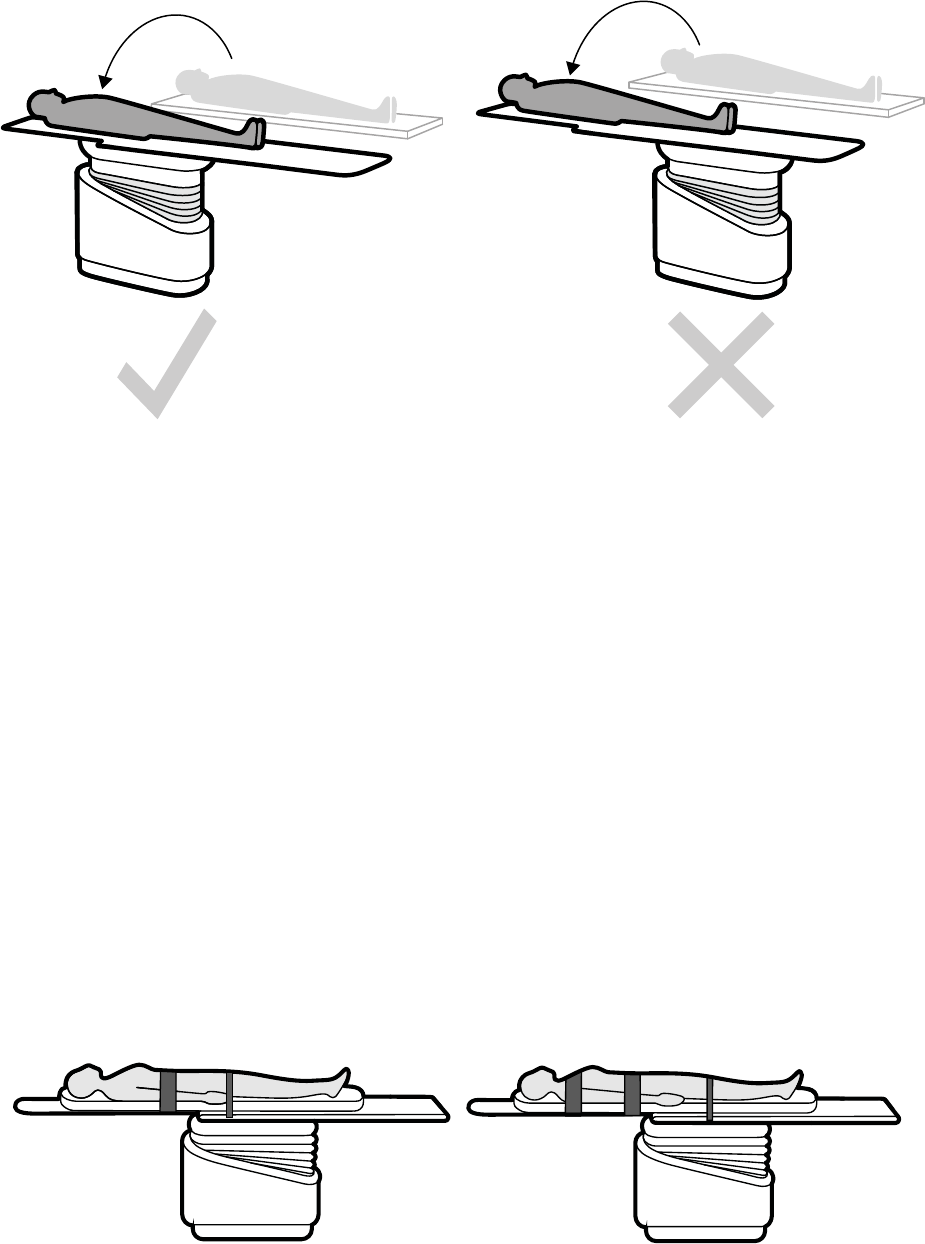

5.8 Układanie pacjenta na stole................................................................................................... 51

5.8.1 Stosowanie pasów ograniczających ruchy pacjenta...............................................52

5.8.2 Zmiana orientacji pacjenta.....................................................................................53